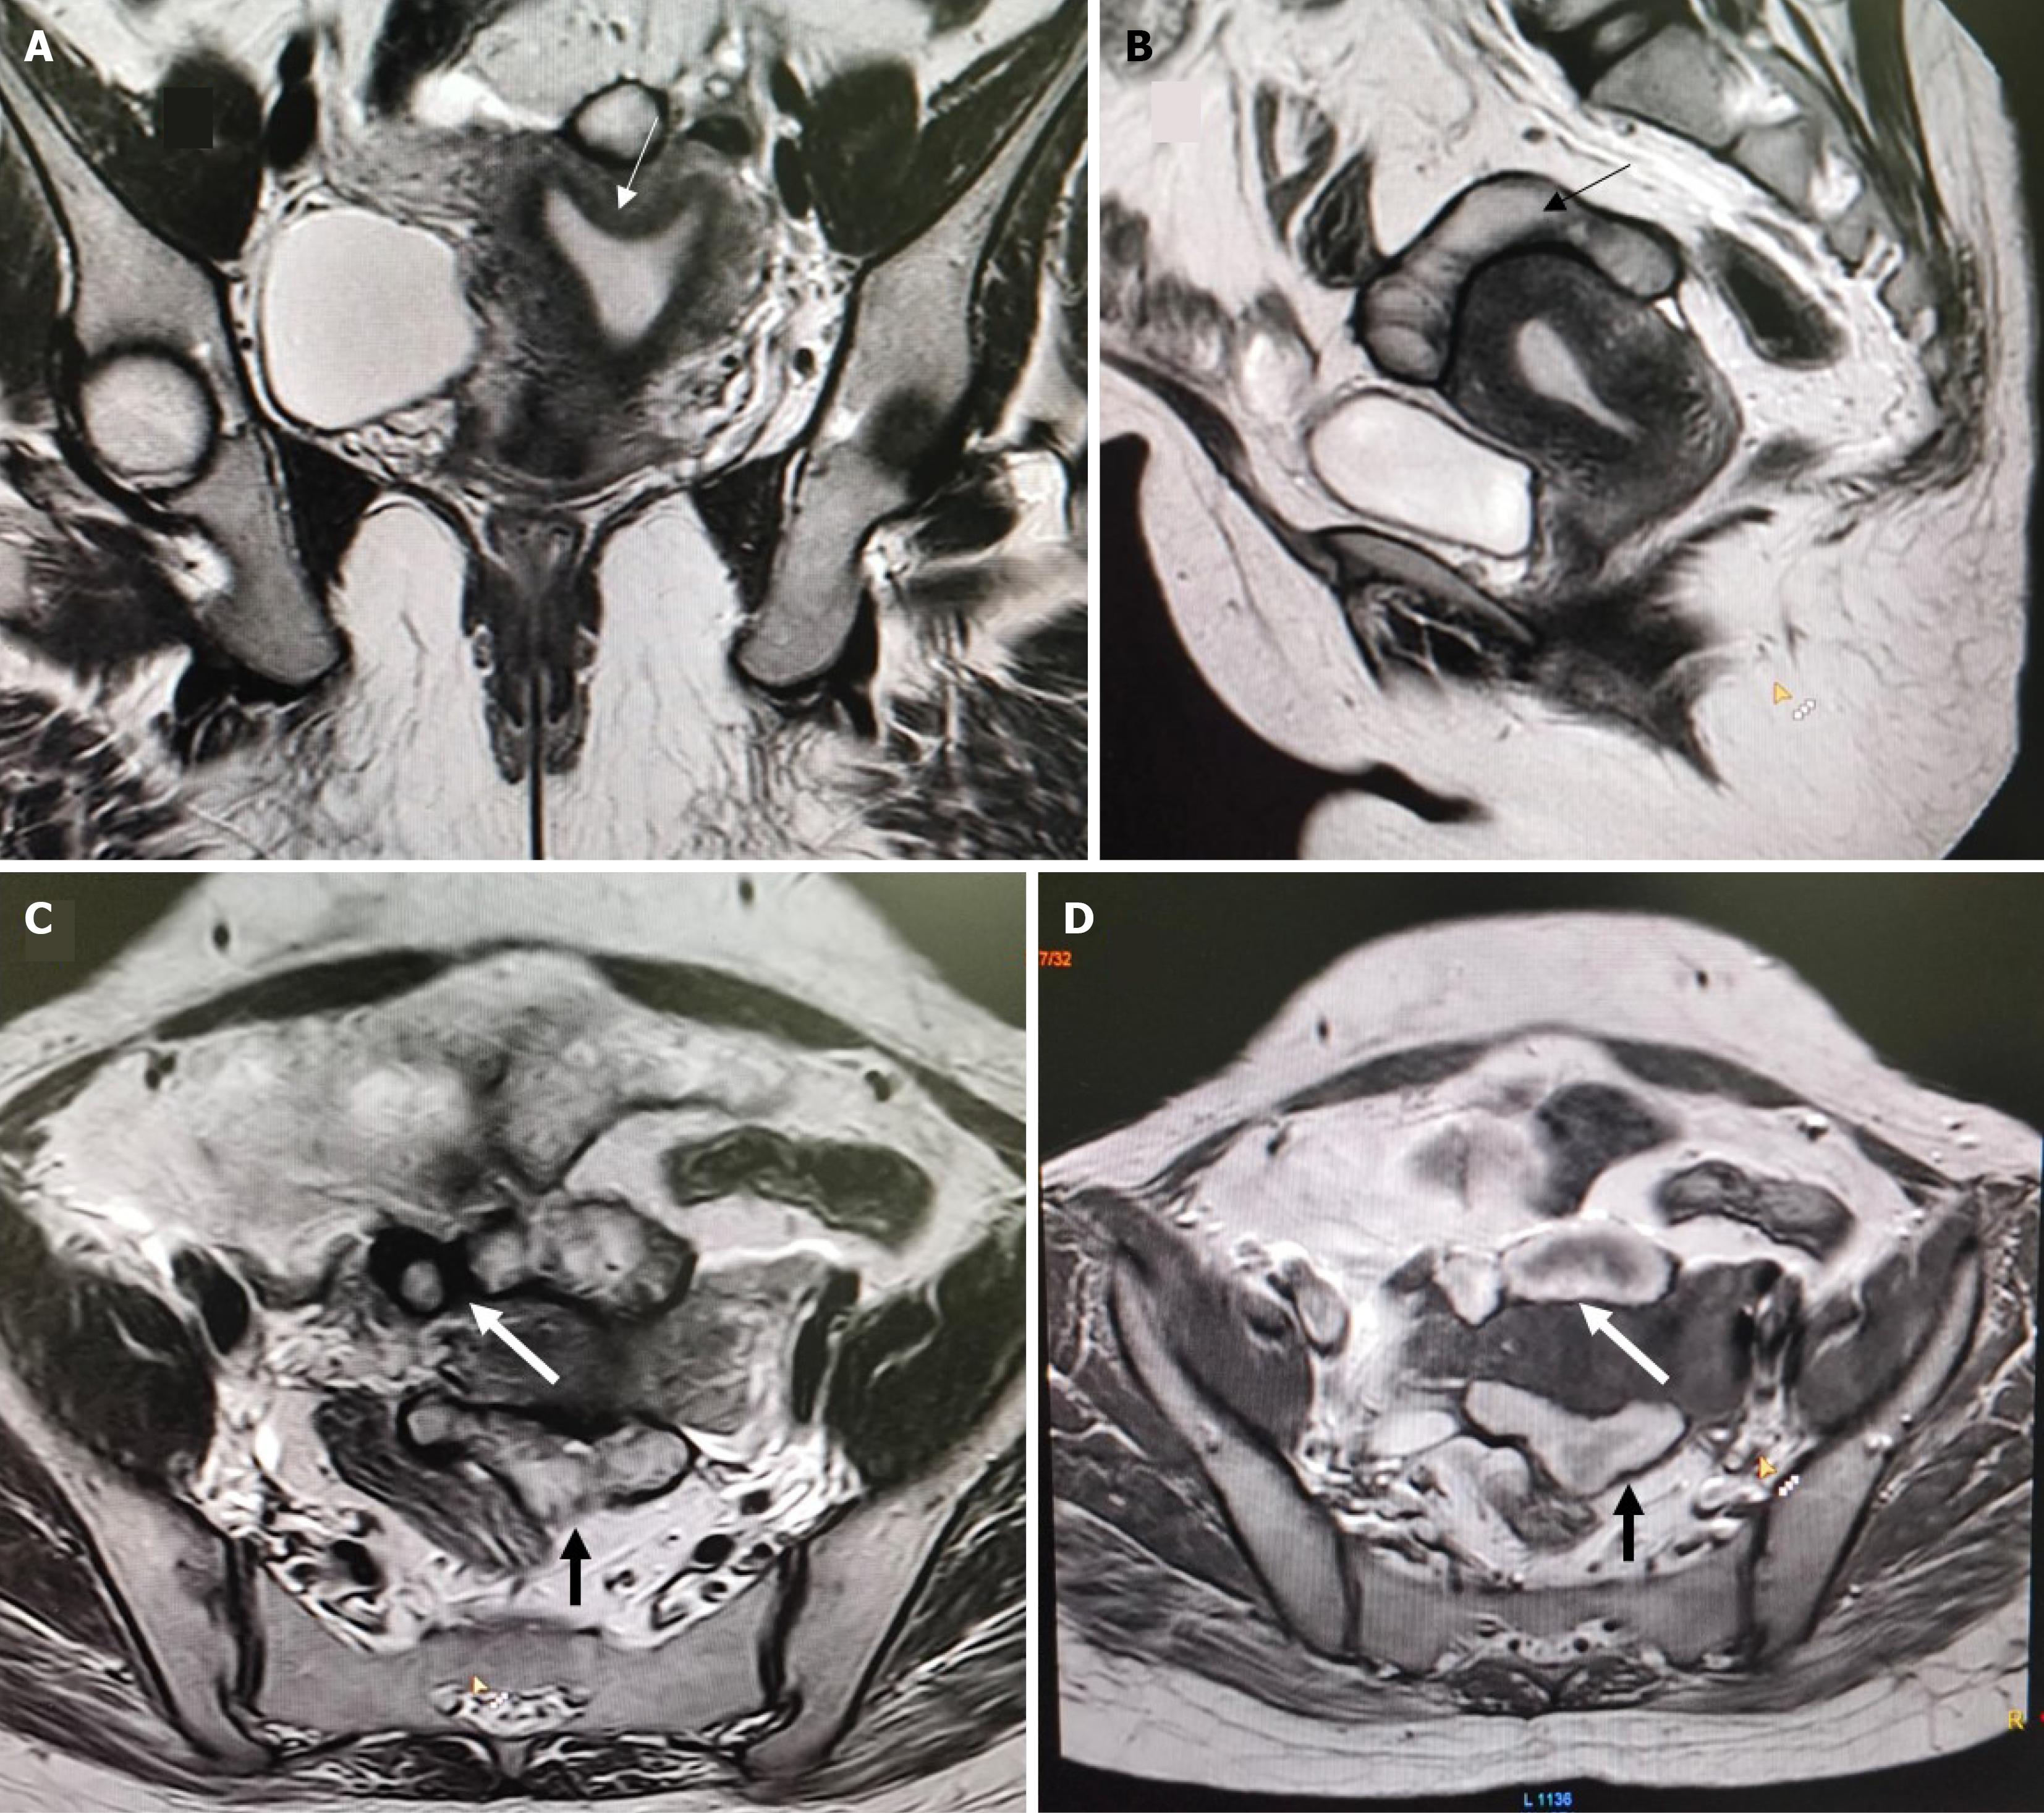

Overall, 22 patients had MRI findings consistent with endometriosis. Peritoneal disease (P1-P3) was not identified in this series. Ovarian endometriomas were present in 16 patients (21.3%), most commonly in the 3-7 cm range (O2, 12 patients; 16.0%). Tubo-ovarian adhesions or involvement (T2-T3) occurred in 11 patients (14.7%) (Figures 1, 2 and 3). Deep endometriosis nodules were observed primarily in the parametrial/uterosacral compartment (B) in 6 patients (8.0%). No rectosigmoid (C) or anterior compartment (A) endometriosis lesions were seen. Adenomyosis was identified in 4 patients (5.3%; diffuse in 2, focal in 2). A summary is presented in Table 2.

Among the 75 patients evaluated, obstruction was identified in 13 patients (17.3%). Within uterine anomaly groups (U), obstruction was most frequent in U3c anomalies, where 6 of 13 patients (46%) demonstrated obstruction. The presence of genital tract obstruction showed a strong correlation with endometriosis, with affected patients demonstrating nearly threefold higher prevalence compared to those without obstruction (61.5% vs 22.6%, P = 0.005). In this subgroup, obstruction affected both endometriosis (3/7; 43%) and non-endometriosis (3/6; 50%) patients. In U0 uteri (arcuate), 2 of 4 patients affected (50%), split equally between endometriosis (1/3) and non-endometriosis (1/1). U4a had obstruction in 1 of 2 patients (50%), single patients showed signs of obstruction in each group of U4b, U5a, U6. It was rare in U2a (1/14; 7%) and U5b (1/25; 4%). Across cervical categories (C), obstruction occurred predominantly in patients with normal morphology (C0), where 10 of 29 patients (34.5%) had endometriosis. In C2, 7 of 14 patients had endometriosis, whereas severe anomalies (C4) were associated with endometriosis in 4 of 29 patients (13.8%). Despite these endometriosis distributions, obstruction overall remained infrequent and did not cluster within any specific cervical subtype. Vaginal morphology similarly showed limited correlation with obstruction. Most patients with normal vaginal anatomy (V0) did not exhibit obstruction, despite 18 of 46 having endometriosis (39.1%). Among those with V4 anomalies, endometriosis was identified in 4 of 29 patients (13.8%). Overall, obstruction occurred sporadically across uterine, cervical, and vaginal classifications. Obstruction was most frequent in U3c (46% of that subgroup) but was distributed among both endometriosis and nonendometriosis patients.